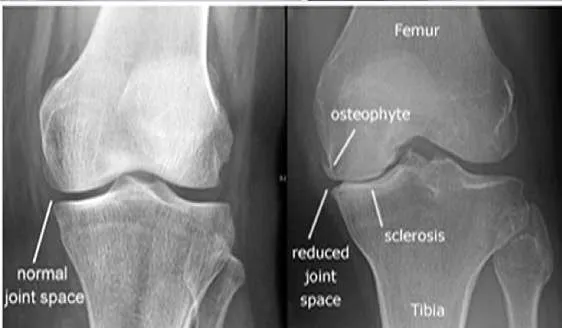

Plain X-ray of the knee for a 60-year-old lady with OA.

- Joint Space Narrowing: Usually asymmetric, often affecting the medial tibiofemoral compartment more than the lateral. 2. Osteophytes: Bony spurs forming at the joint margins (e.g., tibial spines, femoral condyles, patellar edges).

Other findings that may appear - Subchondral Sclerosis: Increased bone density in the bone immediately beneath the cartilage layer. - Subchondral Cysts: Fluid-filled cavities in the bone near the joint surface. - +/- Malalignment: Varus (bow-legged) or valgus (knock-kneed) deformity may develop.

- Diagnosis: Osteoarthritis

Osteoarthritis

- Signs:

- Narrowing the space of joint

- Bone erosion

- Subchondral sclerosis

- Osteophyte formation